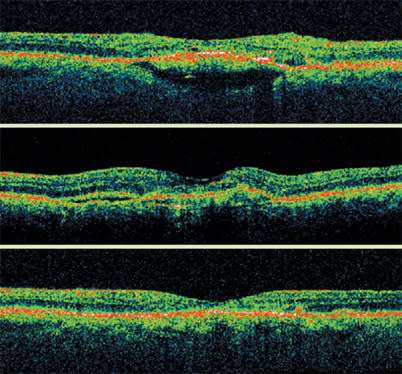

The most common characteristic associated with DME on OCT is sponge-like swelling. In its presence, OCT shows a blunted foveal depression and darker outer retinal layers.

These scans show Stratus OCT images before and after laser treatment for diabetic macular edema. After treatment, the foveal depression returns and the outer retinal layers return to a more normal linear appearance. The outer layers are also less dark, indicating improvement in the sponge-like swelling.